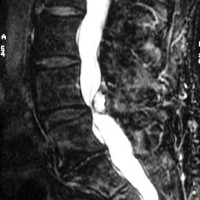

A free medical education seminar series for everyoneA FREE spine education seminar series for everyone Back pain has many faces and to many people it can be distressing, disabling or even frightening. Whether back pain comes from a strain, degenerative disc disease, a herniated disc, spinal stenosis, spondylolisthesis, a complex deformity or even a fracture, there are many options that can help you to live an active lifestyle. Additionally, osteoporosis is another disease that you may not even know you have. Learn from these dynamic experts about the various types of back problems and the latest treatments available. We will discuss the problems, the solutions and leave time for your questions to help you be active. Talk with the experts and get your concerns addressed. Spine Program